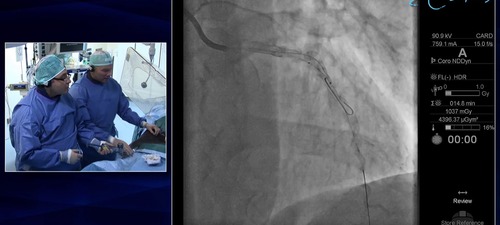

Repeat FFR to LAD following PCI to LMS/LAD

Following PCI to the left main stem and the proximal left anterior descending artery the operators remeasure FFR.  This demonstrates that the lesions in the mid LAD are still positive and in need of further PCI.  The operators proceed to deploy a further stent to improve the physiology and reduce the chance of the patient having angina symptoms.